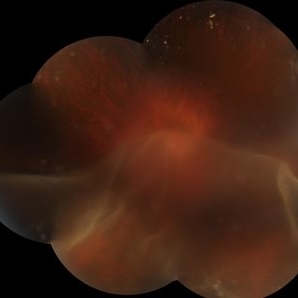

SUNSET THROUGH A VEIL

Oct 12 2023 by Deepti A Kulkarni, M.B.B.S., D.N.B., F.V.R.

HIGH MYOPE WITH A CORRECTION OF -24D. SUDDEN VISION LOSS FOLLOWING TRAUMA.

Photographer: DEEPTI KULKARNI, DR ANIL KULKARNI EYE HOSPITAL, MIRAJ, INDIA

Imaging device: TOPCON

Condition/keywords: GIANT RETINAL TEAR